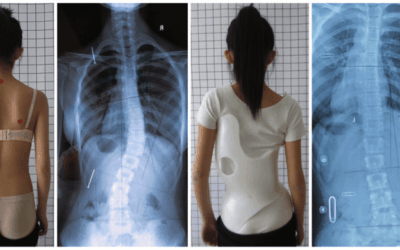

Brace Scoliosis GBW

Didesign sesuai pola kurva skoliosis dan dibuat dengan (tekonologi) scan 3D sehingga menghasilkan koreksi terbaik

Bagaimana Brace 3D GBW bekerja?

Dengan penggunaan Brace 3D GBW, kami melakukan koreksi 3Dimensi. Skoliosis harus dimengerti secara 3Dimensi, karena pada pasien scoliosis, tulang belakang bukan hanya bengkok ke sisi kiri atau kanan, tetapi juga berputar. Untuk pasien scoliosis yang parah, akan...